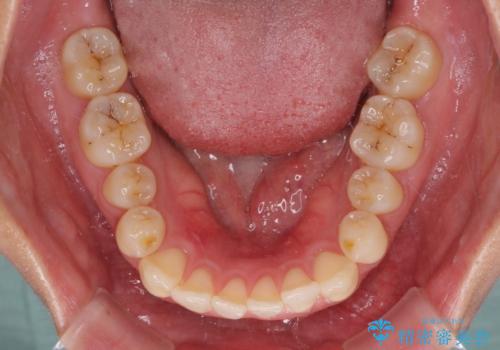

すきっ歯とオープンバイトをインビザラインで改善

- 前歯の上下スペースと前歯の隙間を気にして来院された患者様です。

インビザラインにより上下の前歯の隙間を閉じていくこととしました。

上下の隙間に舌が入り込むことが、すきっ歯やオープンバイトの原因であったため、舌の筋肉のトレーニングも並行して行い、後戻りの抑制を図りました。